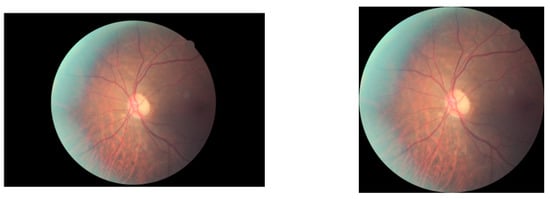

The retinal fundus image data used for training and testing were obtained from three open datasets: EyePaCS [36], DDR [37], and Messidor-2 [38]. We removed some images from EyePaCS because they were overexposed or underexposed, or had lost information. Figure 1 shows several examples of these discarded images. The original images are circled by a wide border on the black background where no information is provided for the DR detection task. Therefore, the extra black border was cropped out to leave the central part of each image containing task-related features. The source and images, the borders of which are removed, are shown in Figure 2. All images were re-sized to 512 × 512 and normalized before being fed into the network. After normalization, the pixels of each channel were in the range −1 to 1, with a standard deviation of 1.

Figure 2.

An example of source (left) and pre-processed (right) images (the image on the left is from the EyePaCS dataset [36]).